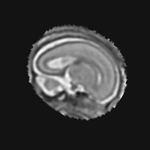

Exp. 2: Fetal brain data is used to test the robustness of our approach under real conditions. Fetuses younger than 30 weeks very often move a lot during examination. Fast MRI sequences allow artifact free acquisition of individual slices but motion between slices corrupts consistent 3D information. Fig. 3 shows that our method is able to accurately predict Ti^^subscript𝑇𝑖\hat{T_{i}} also under these conditions. For this experiment we use ωisubscript𝜔𝑖{\omega_{i}} from three orthogonally overlapping stacks of ssFSE slices covering the fetal brain with approximately 20-30 slices each. We are ignoring the stack transformations relative to the scanner and treat each ωisubscript𝜔𝑖{\omega_{i}} individually. For ΩtrainsubscriptΩ𝑡𝑟𝑎𝑖𝑛\Omega_{train}, 28 clinically approved motion compensated brain reconstructions are resampled into a 150×150×150150150150150\times 150\times 150 volume with 1mm×1mm×1mm1𝑚𝑚1𝑚𝑚1𝑚𝑚1mm\times 1mm\times 1mm spacing. A density of 500 unique sampling normals has been chosen via the Fibonacci sphere sampling method with 25 sampling planes evenly spaced between -25 to +25 on the Z-axis. This gives a plane spacing of 2mm, sampling only the middle portion of the fetal brain. Training took approximately 10hrs for 30 epochs. Prediction, i.e., the forward pass through the network, takes approx. 12 ms/slice.

Figure 3: Comparison of a single slice from a heavily motion corrupted stack of ssFSE T2 weighted fetal brain MRI (a); axial multi planar reconstruction of one sagittal input stack (b); a slice at approximately the same position through a randomly selected training volume (c); failed reconstruction attempt using standard SVR based on three orthogonal stacks of 2D slices (d) (the fetus moved heavily between the acquisition of the individual stacks); reconstruction based on SVRNet Ti^^subscript𝑇𝑖\hat{T_{i}} regression (e); SVR initialised with SVRNet transformations after eight iterations of SVR (f). Note that (e) and (f) are reconstructed directly in canonical atlas co-ordinates.